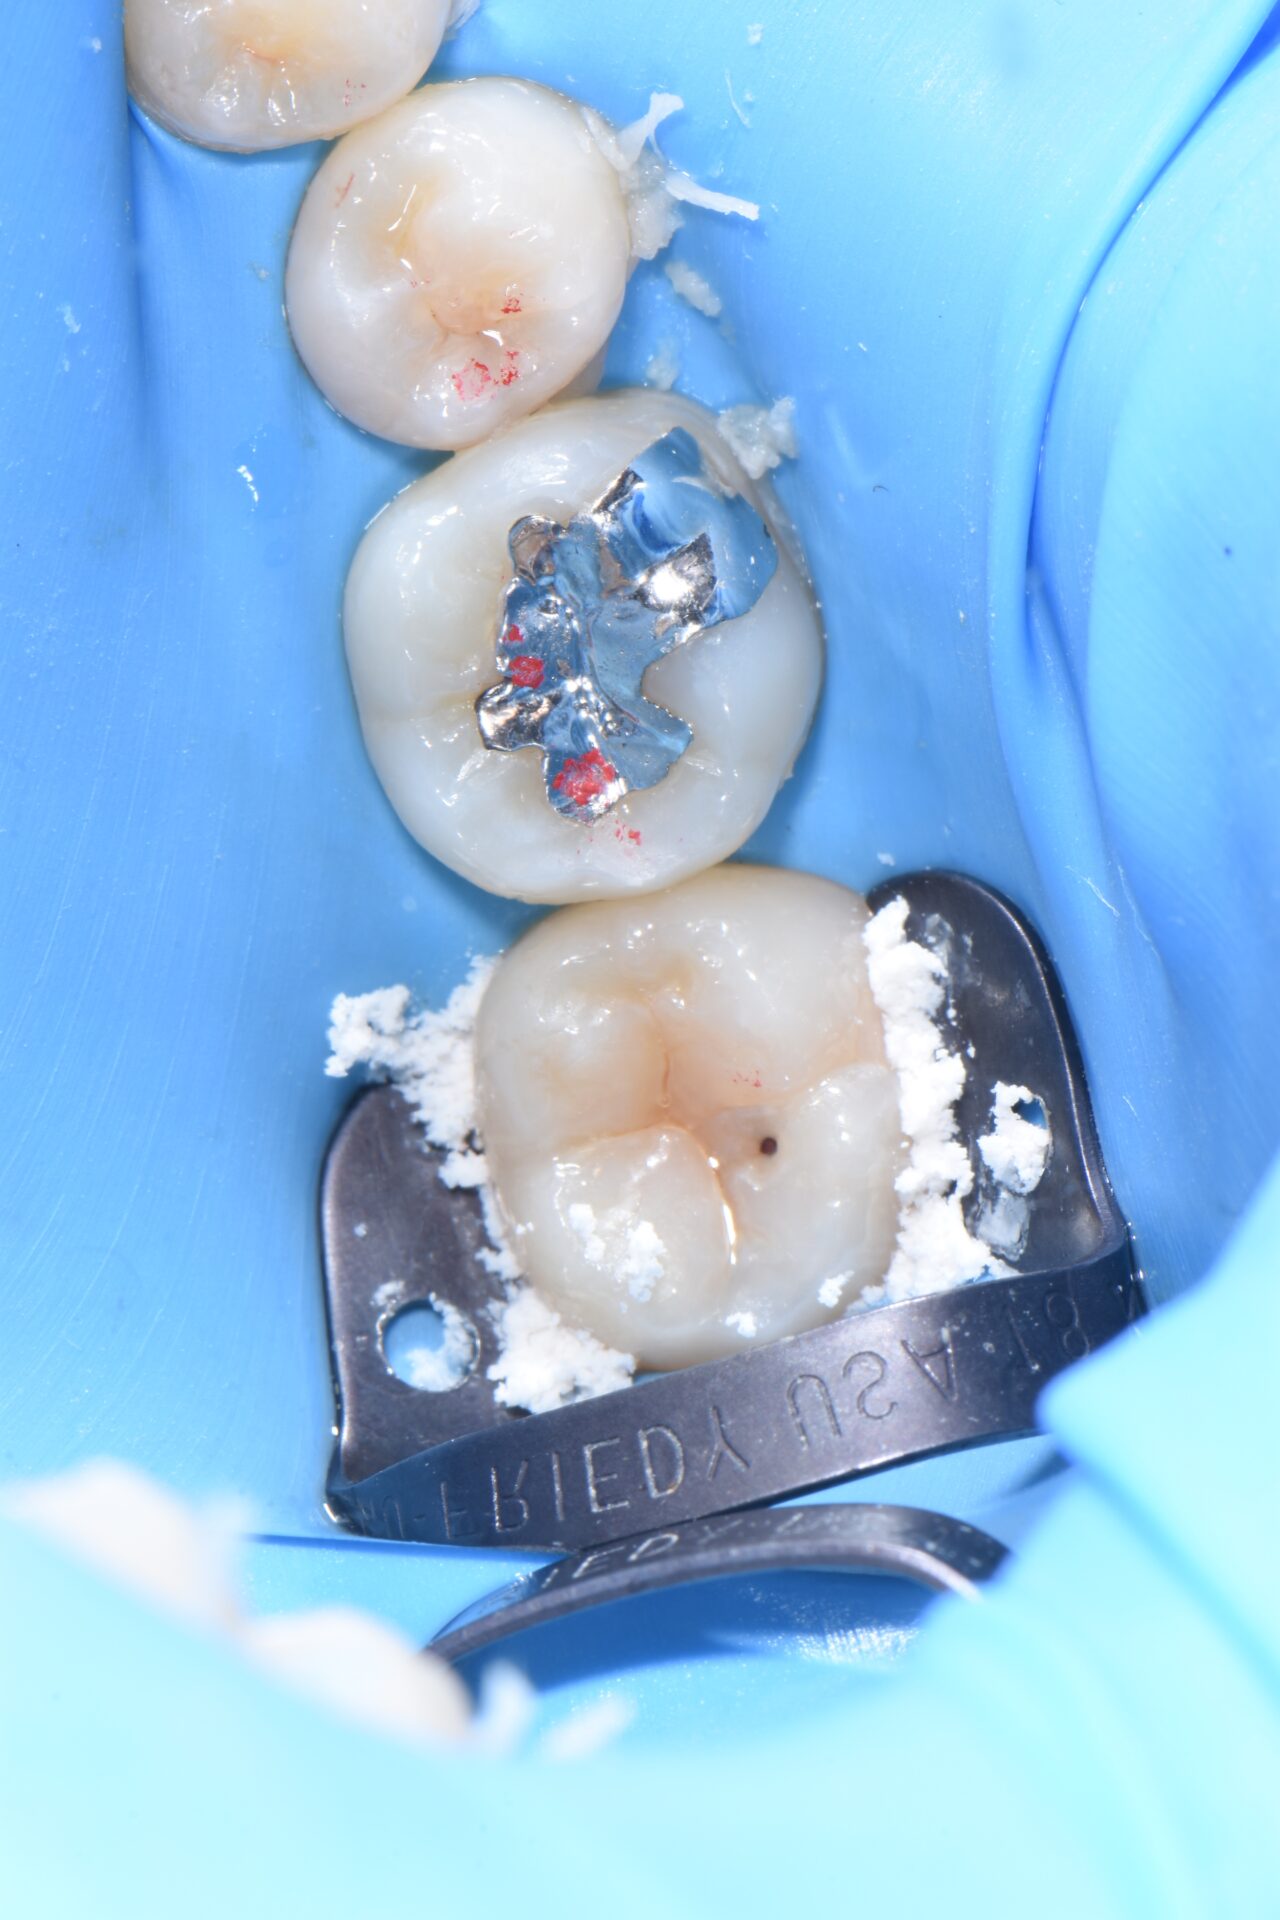

術後 通法に従い、ラバーダム防湿下でダイレクトボンディングにて修復治療